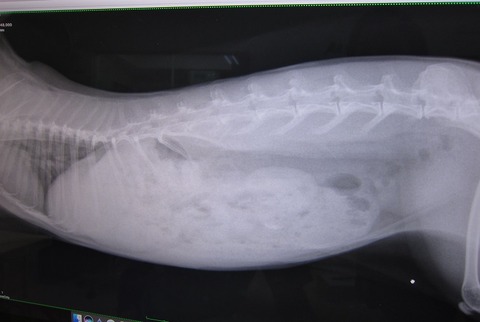

昨夜からの流れを話しし、診察、レントゲン

閉塞所見はありません

もちろん心臓も小さくなってないし

若干のガスはあれど、強いて指摘するならばレベル

と、胃腸に大きな問題はなさげだったのだが…

脂肪、すご過ぎやん…( ̄ェ ̄;)

前回との比較…

前回… とは、最初、あんまりにも食べない食べないで、きちんと痩せた状態、だったので余計かもですが、それでもマズい…

体重の数字や触った感じで気にはなってたから、

ずっとペレットは朝晩5gずつ。…だのに、増える体重、結果こんな…

他にもこんな子ざらにいます、でも、いるからOKて話ではなく、

体質やから仕方ない、って、片付けるには早すぎると思うし、

何より肥満って何かにつけてリスクの確率は通常より上がるしな。